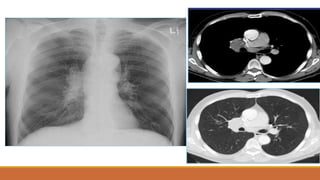

TDMP lượng ít

TDMP lượng vừa

TDMP lượng nhiều